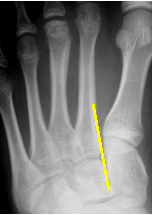

The normal midfoot